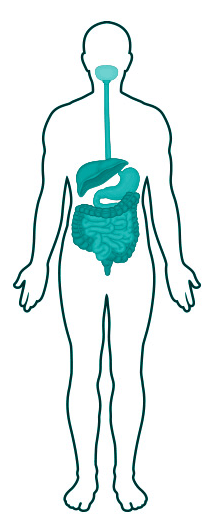

A parasite is a micro- or macro-organism that needs to satisfy its vital nutritional requirements by feeding off certain host tissues or body fluids that contain the specific biochemicals that it needs. There are parasites for every single tissue of the human body, once they gain access. An intestinal parasite has to gain access via the oral cavity with contaminated food or drink if it is to cause infection. Other portals of entry are irrelevant. Eight ways by which humans can contract parasitic infections are briefly summarized below.